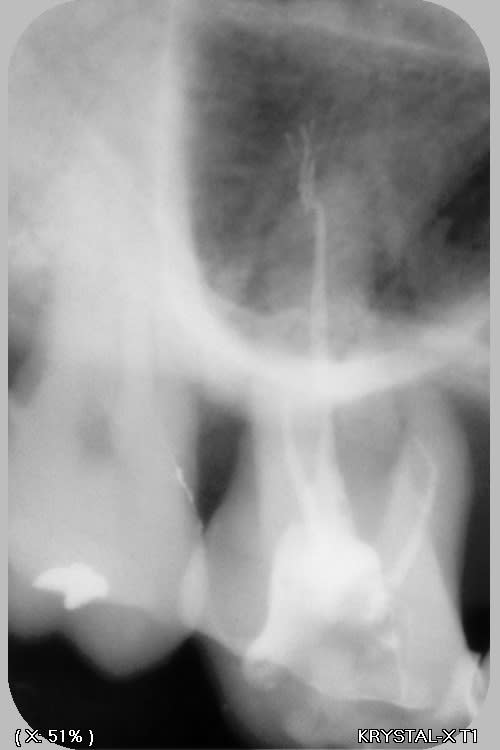

j'ai trouvé ça...rien de parfait malgré l'utilisation de broches manuelle, en alternance avec les rotatives sur certaines racine "légèrement coudées"....

pano et scan plus tard